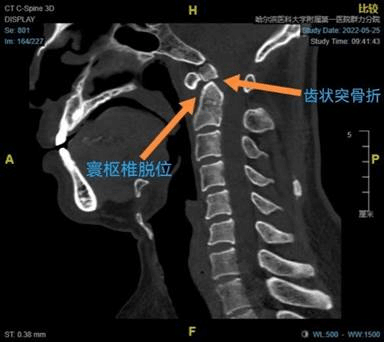

术前CT矢状位术后CT矢状位

在仔细研判张先生受伤及治疗过程,完善相关检查后赵伟教授发现,张先生在外伤后发生了寰枢椎脱位,导致脊髓受压产生四肢瘫的症状。对于确认的寰枢椎脱位,最佳的治疗方法是通过外科手术来恢复寰枢椎的正常解剖结构及稳定性。

寰枢椎部位是人体神经血管较为密集的区域,手术风险极高,手术难度极大。为了确保患者的生命安全,赵伟教授团队做了详细、充足的术前准备,并根据术前三维CT结果制定寰枢椎钉棒系统复位、植骨融合固定的手术方案